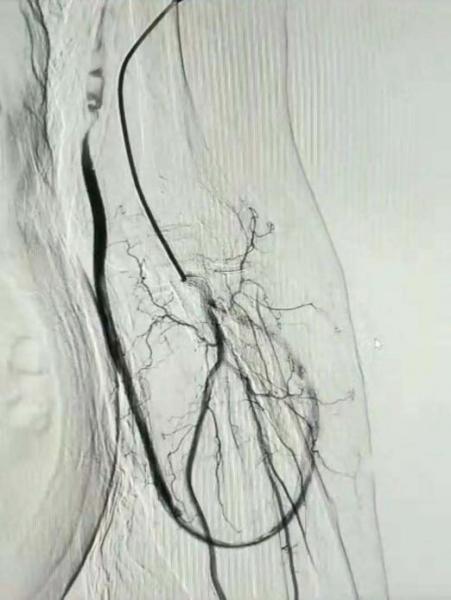

患者路某某,因尿毒症规律透析治疗多年,于1年前行人工血管动静脉瘘成形术,长期以人工血管行透析治疗,近日,因发现人工血管震颤减弱来我院介入血管科就诊。

术前B超检查提示:左上肢贵要静脉、环形人工移植血管环内实质性低回声。介入血管科副主任丁文金经综合评估,反复研究讨论,并与患者及家属充分沟通后,结合患者目前情况,决定采用介入接触性溶栓、血管球囊扩张成形的手术方式开通血管通路。

术中由丁文金主刀,带领介入血管科团队顺利为患者进行了接触性导管溶栓及狭窄段血管PTA球囊扩张成形术,术后持续行接触性溶栓治疗,再次复查造影提示动静脉瘘通畅性良好,术后患者动静脉瘘震颤恢复良好,后期行人工血管透析血流量良好治疗顺利,患者病情恢复良好出院。